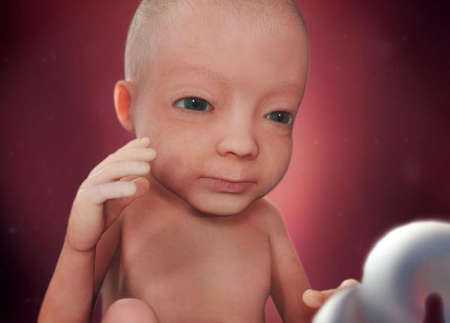

Пропорции тела ребенка аналогичны пропорциям новорожденного. Вес ребенка на 27 неделе беременности составляет 800-900 г, а рост около 32-33 см. Длина стопы вашего малыша может достигать 2 см. Чтобы легче было представить, малыш напоминает по размерам фрукт помело или школьный глобус.

Кожа малыша еще очень тонкая и сморщенная, так как он находится в водной среде. А пушковые волосы на теле начинают темнеть. Наступает и решающая стадия в развитии коры головного мозга. Нейронные связи становятся более активными и готовят почву для полноценного развития ребенка после его появления на свет. Благодаря этому, у ребенка продолжают закладываться режимы сна и отдыха. И уже сейчас ваш малыш ведет себя, как новорожденный, он может засыпать и просыпаться в определенное время и подолгу играть с пуповиной или своими конечностями.

Основные черты личика вашего малыша уже сформировались, теперь он будет набираться сил и готовиться к предстоящим родам. Глаза вашего крохи уже открыты, он может моргать с определенным интервалом и видеть свет через стенку живота. Ваш малыш уже более осознанно может двигать своими ручками и ножками. Он может с интересом наблюдать, как сжимаются и разжимаются его пальчики, и класть их в рот.

Вес ребенка на 27 неделе равен 900 граммам, а его рост составляет 30-35 см. Ребенок спит почти 20 часов в сутки, но часто просыпается, чтобы перевернуться и передать привет маме.

На 27 неделе беременности мамочкам всегда интересно знать, что же происходит с их долгожданным плодом. Можно отметить несколько основных моментов.

- Вес малыша около 1 кг, а рост примерно 35 см.

- С каждым днем малютка становится все симпатичнее. Его жировая прослойка утолщается, складки на теле пропадают. Если на 27 неделе сделать УЗИ, то фото малыша отразит эти изменения.

- Глаза уже приоткрыты, а реакция на свет острее. Если направить на живот яркий свет, малыш повернется.

- Кроха может надувать щеки, сжимать кулачки.

- Ребенок чувствует боль, совершенствует умение сосать и глотать.

- Активно развивается область мозга, ответственная за мышление и сознание.

Что происходит с плодом за пару месяцев до ожидаемых родов? Ребенок достигает «внушительных» размеров: он весит от 800 до 1000 г, а его рост равняется примерно 35-38 см. Вес плода в 27 недель беременности может быть и чуть больше и немного меньше, все зависит от индивидуальных особенностей. Расположен плод может быть как головкой, так и ножками вниз: он еще до конца не «определился» со своим положением.

К этому времени малыш становится похож на новорожденного. Его тело пропорционально, но еще худое. С этой недели подкожный жир только начинает запасаться. Поэтому скоро эпителий не будет выглядеть сморщенным и кожа станет белее гладкой.

К этому времени малыш становится похож на новорожденного. Его тело пропорционально, но еще худое. С этой недели подкожный жир только начинает запасаться. Поэтому скоро эпителий не будет выглядеть сморщенным и кожа станет белее гладкой.

Пушковые волосы темнеют, начинают развиваться волосяные фолликулы. Личико полностью сформировано, на нем можно различить индивидуальные черты. В этот период не развиты только щечки.

В среднем на сроке 27 недель рост плода составляет около 35 см и более, вес достигает 1000 г. Его ножки скрещены, а ручки прижаты к груди. Что, однако, не мешает ему переворачиваться – места в матке для свободных движений еще достаточно. Эти упражнения становятся все ощутимее и заметнее внешне, когда на животе беременной выпирает ладошка или маленькая пятка. На этом сроке малыш обычно занимает положение головой вниз, в котором остается до момента рождения.

Вот так выглядит плод на двадцать седьмой неделе:

Полный рост плода составляет примерно 34 см (от макушки до пяточек) вес около 1 кг.

Плод продолжает набирать массу, необходимую для жизни вне утробы матери. К концу шестого акушерского месяца вес малыша достигает отметки в 850-950 грамм. Рост будущего ребенка увеличивается не так быстро, на двадцать седьмой неделе беременности он составляет 34 сантиметра.

Лицо малыша приобретает черты взрослого человека. У ребенка уже имеются оформленные глаза, губы, ноздри. К началу третьего триместра у плода наблюдается развитие хрящей носа и наружного уха, малыш имеет реснички и брови.

К концу шестого акушерского месяца тело будущего ребенка становится все более похожим на новорожденного. Мальчики и девочки имеют сформированные наружные половые органы. На кожном покрове все еще находятся пушковые волосы, которые к концу третьего триместра начинают темнеть.

Верхний слой эпидермиса сморщен, но наблюдается его постепенное расправление. Окраска кожи сменяется с ярко-красного цвета на розоватый оттенок. На данном сроке начинается активное отложение жировой клетчатки под дермой.